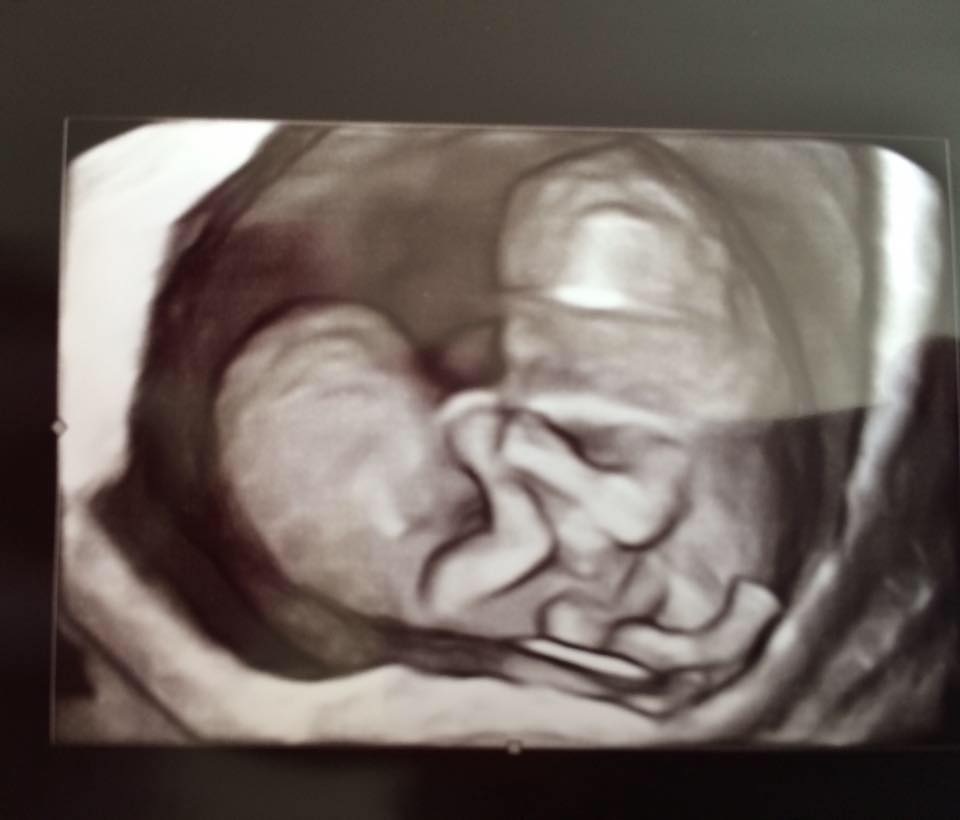

Pregnant Mom S Ultrasound Reveals Twin Babies Kissing Inside Womb Abc News

Unbelievable Ultrasound Pic Of Twins Kissing In The Womb Has Us Swooning Today S Parent